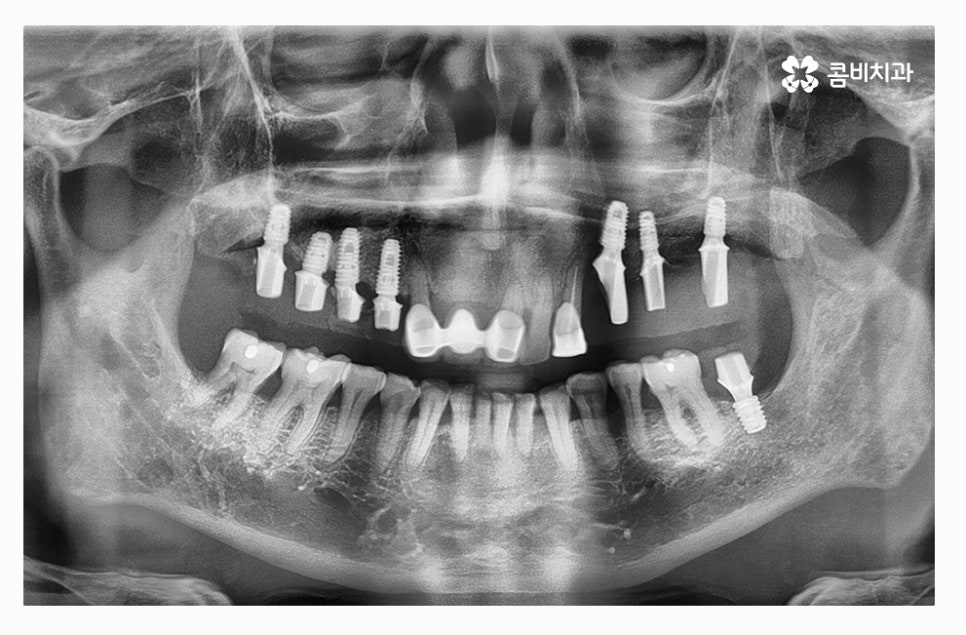

전체임플란트를 해야 할 때 주의사항은 잇몸을 최대한 보존하고

임플란트를 한꺼번에 식립해야 하기 때문에 3D CT 등을 활용한

정밀검진부터 철저하게 해야 하고 식립 각도 하나하나에

철저해야 하기 때문에 의료진의 경험과 실력이 중요한 시술이라 할 수 있어요.